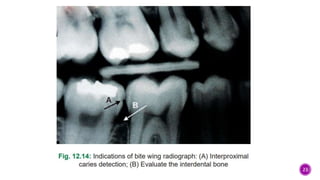

Bitewing Radiography

 Developed by Howard Raper in 1925

 Periapical films are used to record the

coronal portions of both maxillary and

mandibular teeth in one image

 Size 1 film is used in children and size

2 films are used in adults

 Used mostly to detect interproximal

caries and to check the level of bone